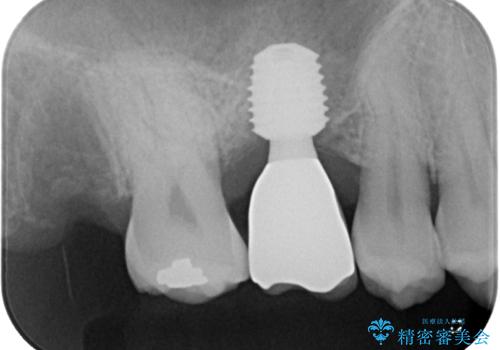

インプラント処置は、抜歯即時埋入を行い、十分な安定性が確認できたため、当日仮歯を装着しました。

インプラントが生着するのを待っている間に反対側の根管治療を行い、左右同時に補綴治療を行いました。

補綴治療後3ヶ月での経過は良好で、引き続き経過観察を行っていきます。